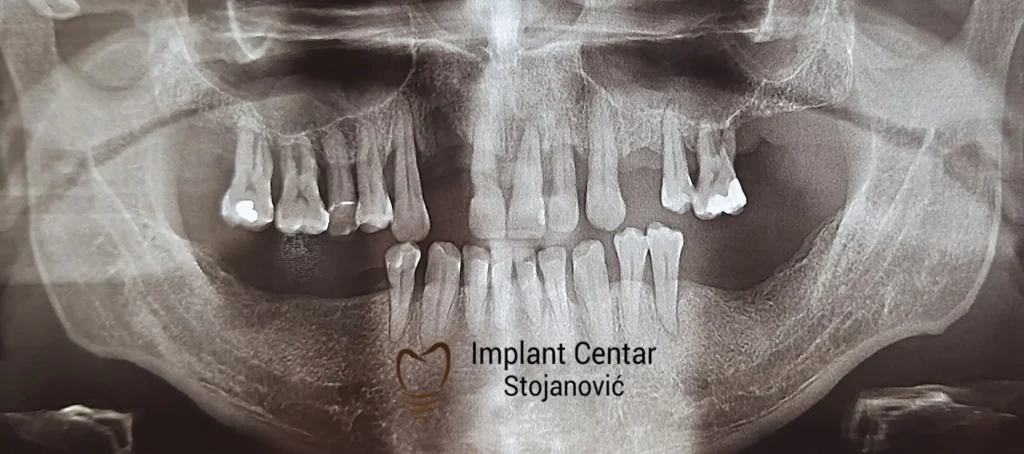

Pacijent sa rascepom usne, nepca i alveolarnog grebena uspešno je rehabilitovan fiksnim protetskim radom na implantatima. Pre dolaska u našu ordinaciju, pacijent je u gornjoj vilici nosio totalnu protezu preko preostalih zuba, dok je u donjoj vilici bio zbrinut parcijalnom mobilnom protezom. Tokom višegodišnje potrage za adekvatnim rešenjem, pacijent nije uspeo da pronađe zadovoljavajuću terapijsku opciju ni u zemlji ni u inostranstvu.

Nakon detaljnog kliničkog pregleda i analize radioloških snimaka, izrađen je sveobuhvatan plan terapije sa ciljem uklanjanja mobilnih proteza i postizanja maksimalne funkcionalne i estetske rehabilitacije. Zbog loše biološke vrednosti preostalih zuba, doneta je odluka o njihovom vađenju i ugradnji dentalnih implantata.

Poseban terapijski izazov predstavljalo je premošćavanje defekta nastalog usled rascepa, kao i ograničena količina raspoložive kosti u gornjoj vilici. Primenom većeg broja implantata i odgovarajućih procedura nadoknade kosti, postignuta je stabilna osnova za fiksni protetski rad.